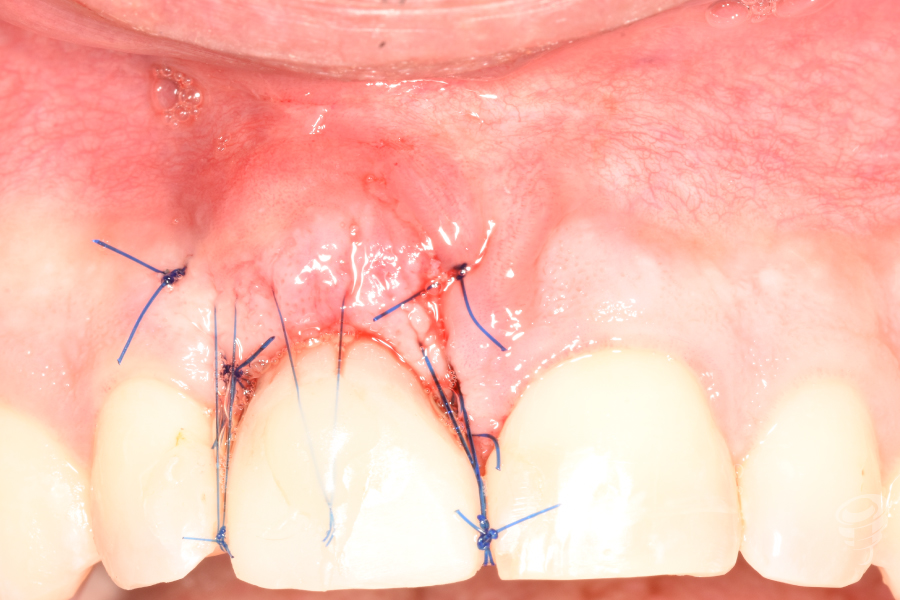

- Injerto óseo: Colocación de partículas xenogénicas y de fresado propio en el gap vestibular y coronal al implante. Injerto de tejido conectivo: Obtenido de la tuberosidad. Injerto subepitelial tunelizado vestibularmente al implante y suturado con Seralene 5-0.

- Provisionalización: Pilar titanio personalizado + corona provisional de resina acrílica (sin contacto oclusal), con la colocación de puntos suspensores para estabilizar la encía y márgenes gingivales.